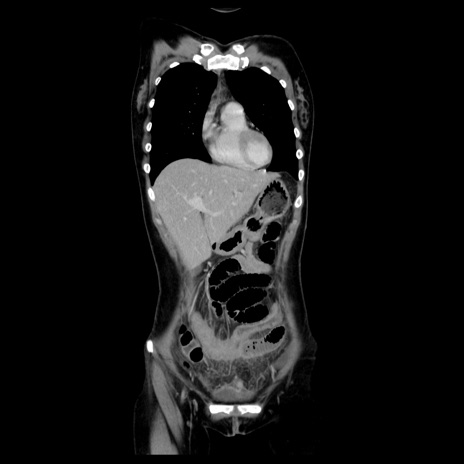

症例39(冠状断像)

【症例】40歳代女性

【主訴】上下腹部痛

【現病歴】2日目から下腹部痛あり。夜間は痛みで眠れなかった。昨日より上腹部痛と下痢が出現。臥位で痛みは軽快したため、休んでいた。本日になって臥位でも立位でも痛みが強くなってきたため救急要請。

【既往歴】子宮内膜症

【身体所見】部:平坦・軟、左上下腹部に圧痛あり、反跳痛あり。

【データ】WBC 21800、CRP 26.78

CT